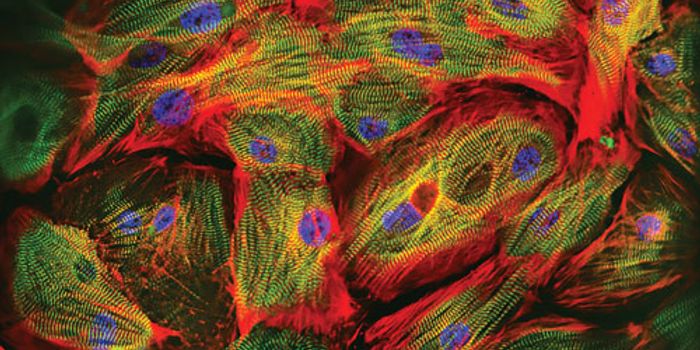

FEB 08, 2016CardiologyAccording to the Heart Foundation, every 34 seconds an American has a heart attack. The cells of the heart, called cardi ...

MAR 10, 2016CardiologyHeart attacks have the potential to kill over a billion cells, and scientists are looking for the best way to replenish ...

MAR 25, 2015CardiologyWorking with lab animals and human heart cells, scientists from Johns Hopkins and other institutions have identified wha ...

FEB 12, 2016Health & MedicineResearchers have transformed mouse fibroblasts, the most common type of cell in mammalian connective tissue, into induce ...